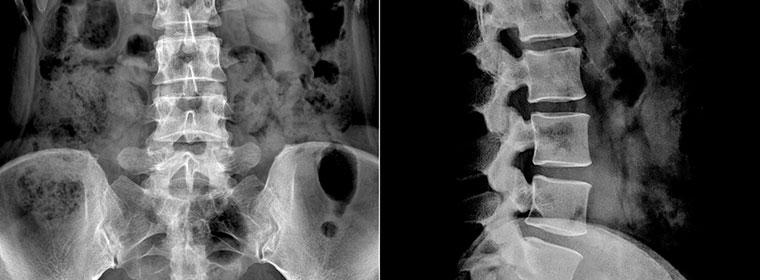

In one case handled by The Schlachter Law Firm, a woman presented with a large, calcified T 8-9 herniated disc just off the midline. The disc compressed the spinal cord and the patient was developing leg weakness consistent with what is known as myelopathy.

The spine surgeon failed to recognize that the herniated disc was calcified and in a position that made it difficult to safely approach the removal of the disc from the back or the side. The only safe approach was to remove this disc through the frontal lateral approach, that is, through the chest. In this case, this surgeon made a very bad choice, exposing the patient to increased risk of spinal cord injury when he elected to use a posterior partially lateral angle to decompress the spinal cord. He did in fact injure the spinal cord when it was avoidable. What is interesting in this case was that the doctor’s expert witness testified contrary to what is in the medical literature about this condition.